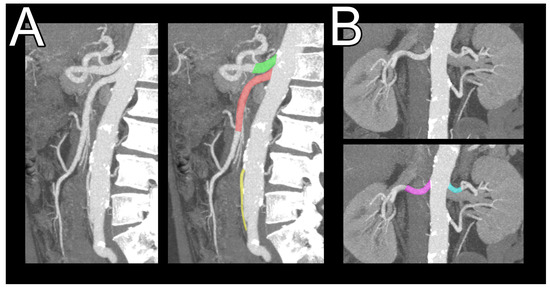

3.5. Abdominal Aortic Branch Adaptation in Patient with Mesenteric Ischemia